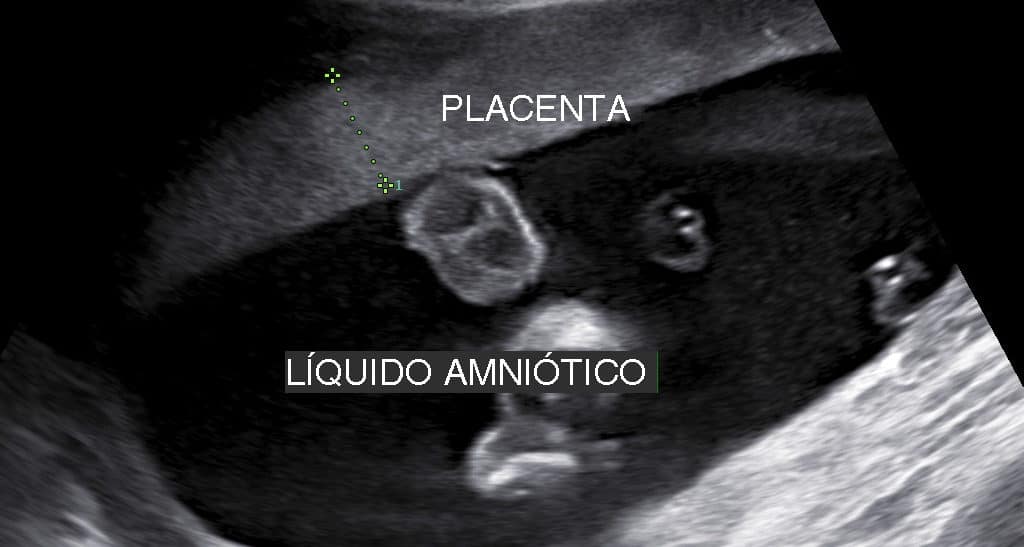

O líquido amniótico desempenha uma série de funções importantes para o feto. Além de proteger o bebê contra traumatismos ele permite o desenvolvimento muscular o…

Intervalos de Referência para o Índice de Líquido Amniótico (ILA) Intervalos de Referência da Medida da Espessura da Placenta

O líquido amniótico é o fluido que envolve o bebê em desenvolvimento e preenche a bolsa e cavidade uterina. Quando a bolsa rompe é esse…